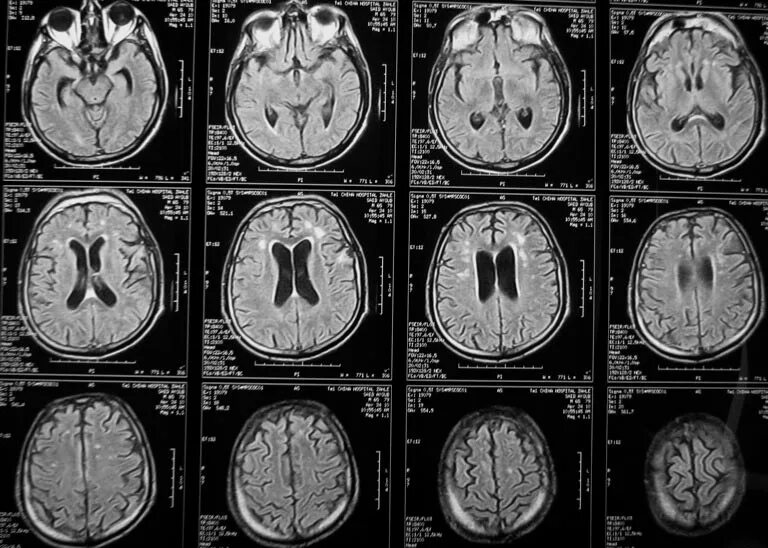

Кт пример